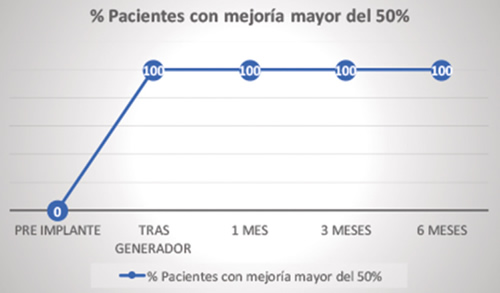

Todos los pacientes a los que se les implantó el generador tuvieron una mejoría del dolor superior al 50 % y esta cifra se mantuvo en el tiempo (Figura 7).

Fig. 7. Porcentaje de pacientes con mejoría mayor del 50 % tras el implante definitivo (n = 8).